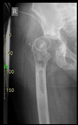

The radiological examination allowed us to verify the close bone-to-implant contact and the unchanged position of the implant during follow-up.

In all the cases operated with the above-described targeting procedure, the stems of the cups remained between the cortical bone surfaces without perforation of the linea terminalis, as shown by postoperative radiographs. There were no complicated surgical situations. In 16 cases, the wound healings were uneventful, and the hips were able to bear weight again after postoperative rehabilitation.